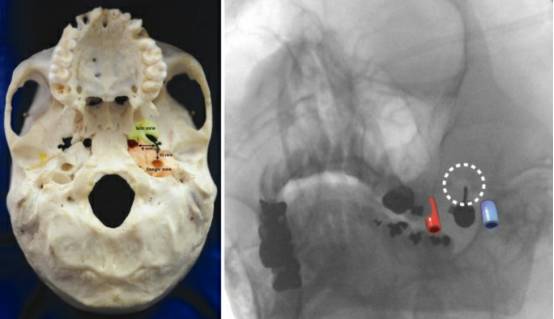

图2. 进针操作轨迹安全区(绿色)和危险区(橙色)(左图)。平行于穿刺针拍摄的术中X线斜位片显示左侧颈内动脉和颈静脉的大致位置(右图)。